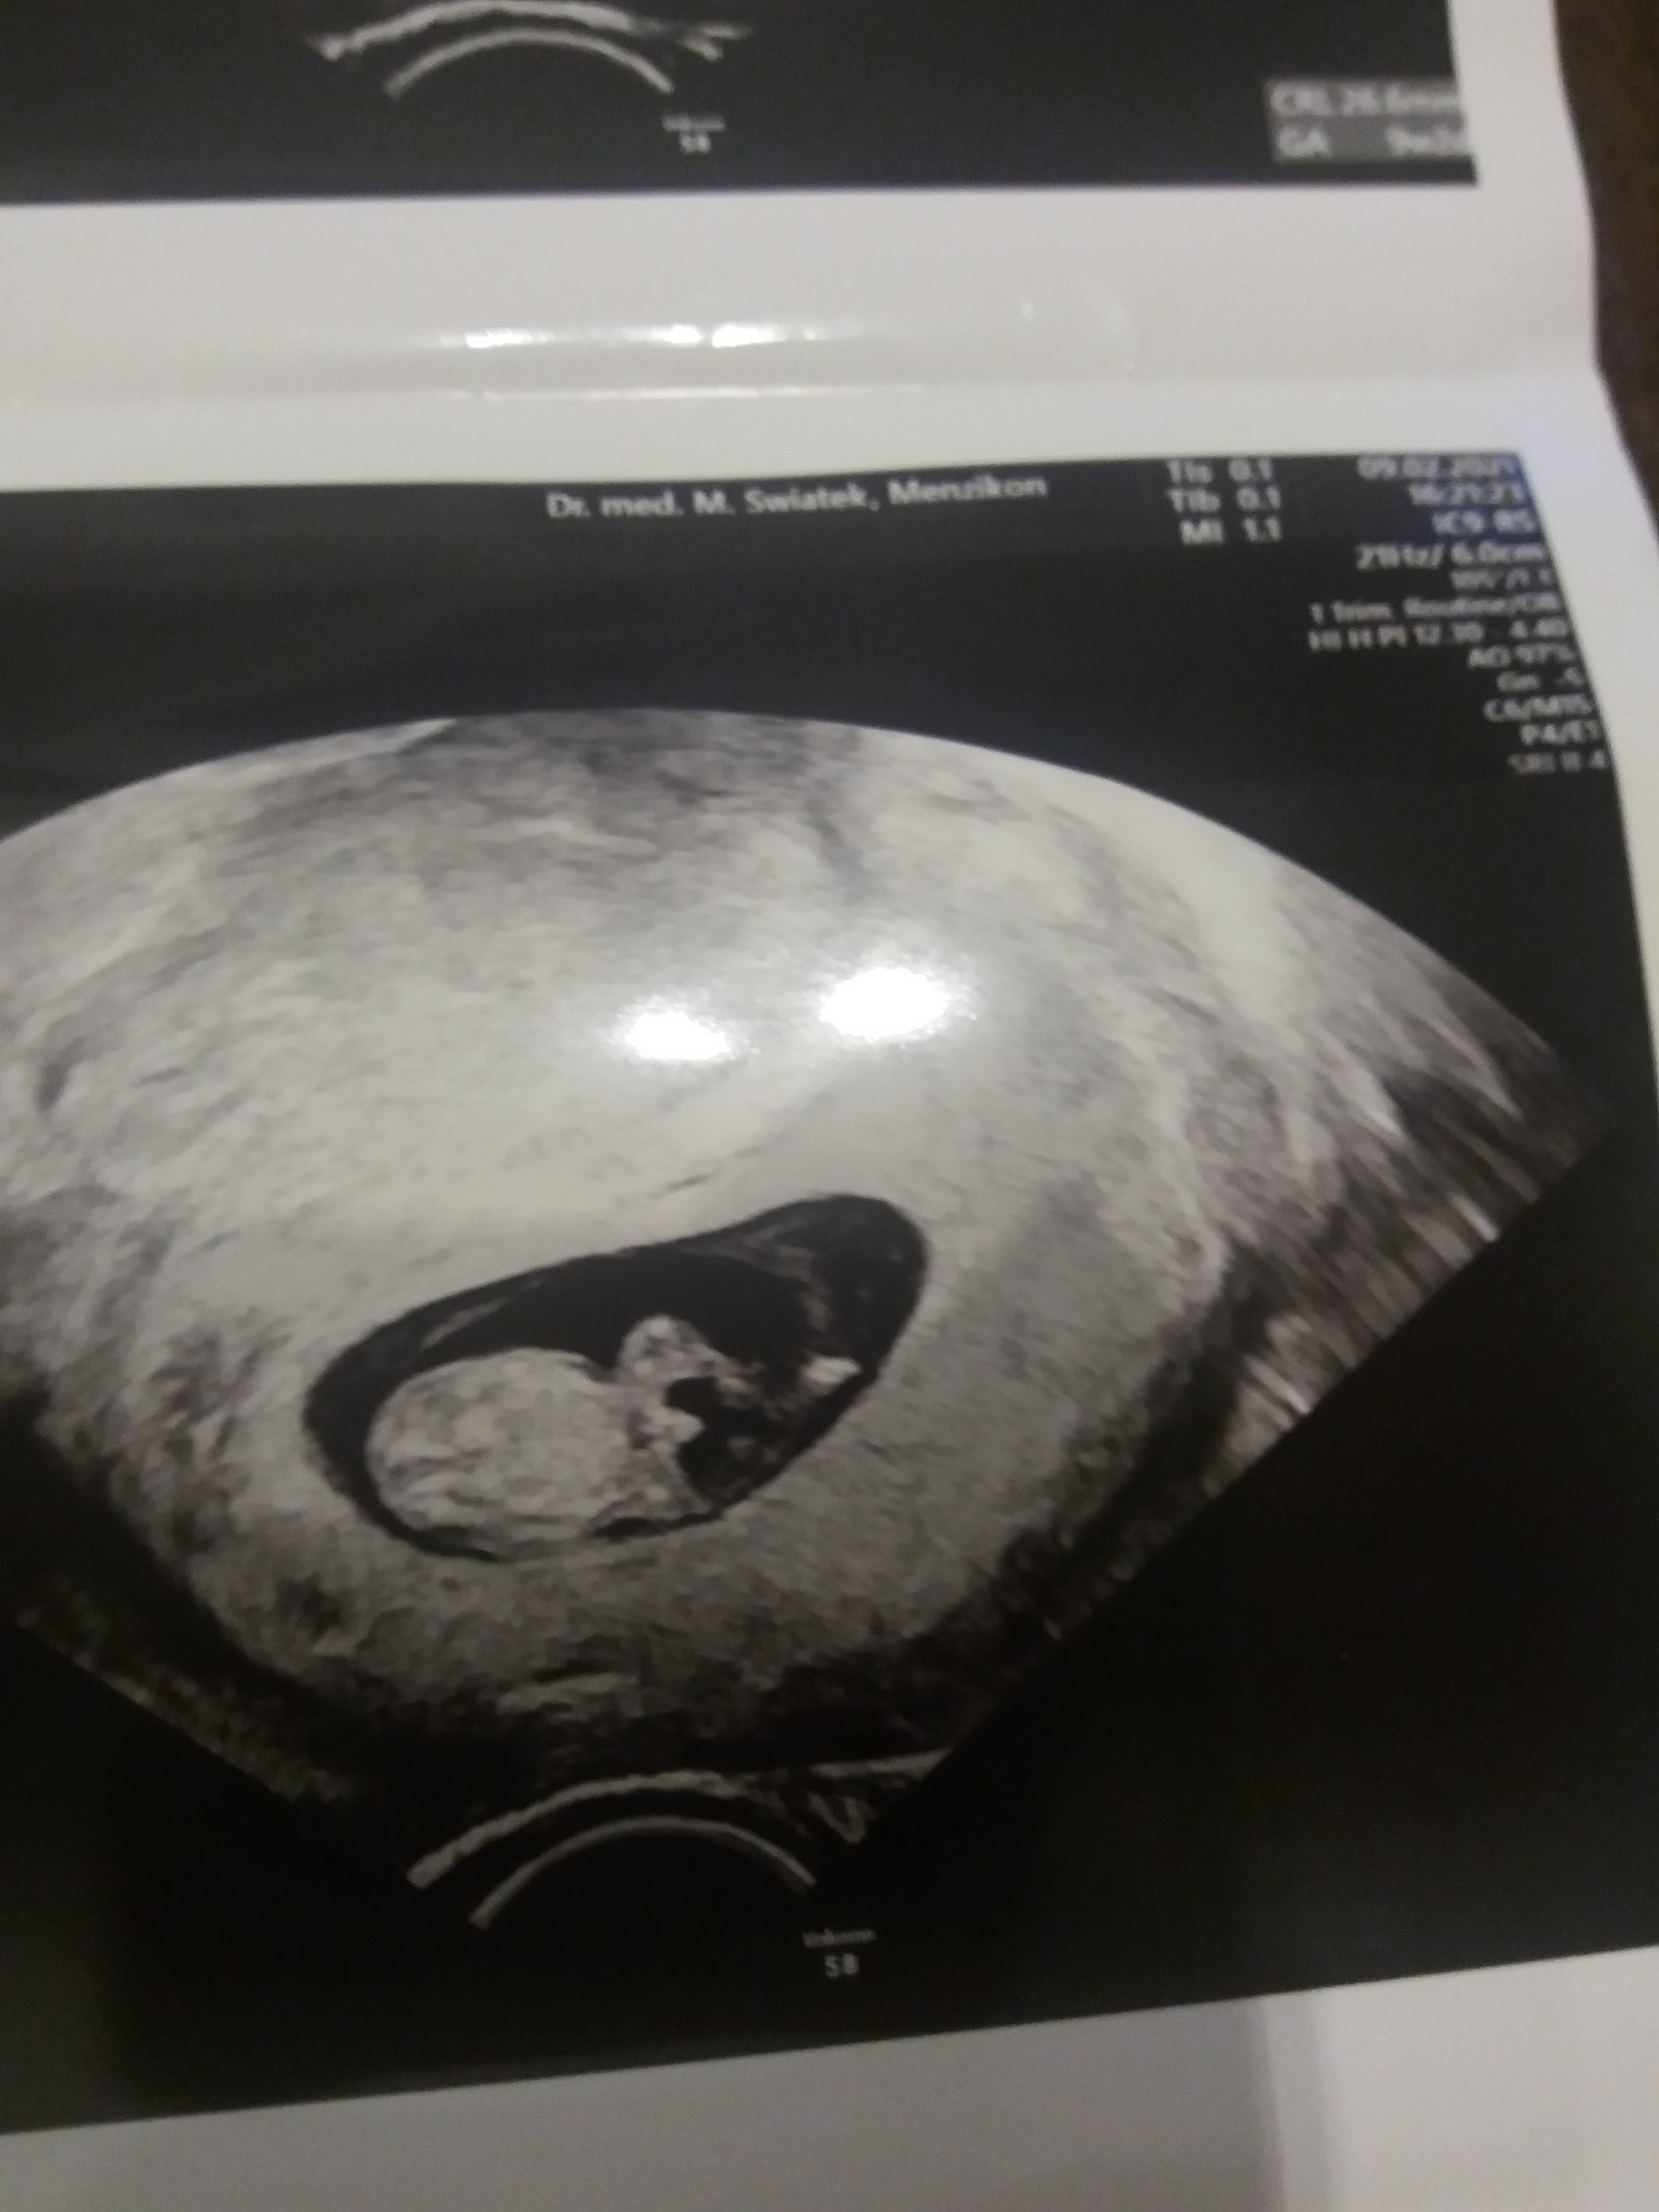

Witam w 19 tygodniu ciąży dowiedziałam się ze będę miała dziewczynkę w 20 tyg okazało się jednak , że to chłopak. Sama już nie wiem bo na jednym usg widać na pewno dziewuche a na drugim chłopca. Może to pempowina ?? Może ktoś mi pomoże rozwiązać ta zagadkę